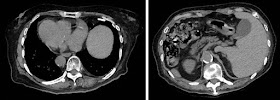

熱源検索のために行ったCTで完全内臓逆位(complete situs inversus)を確認した